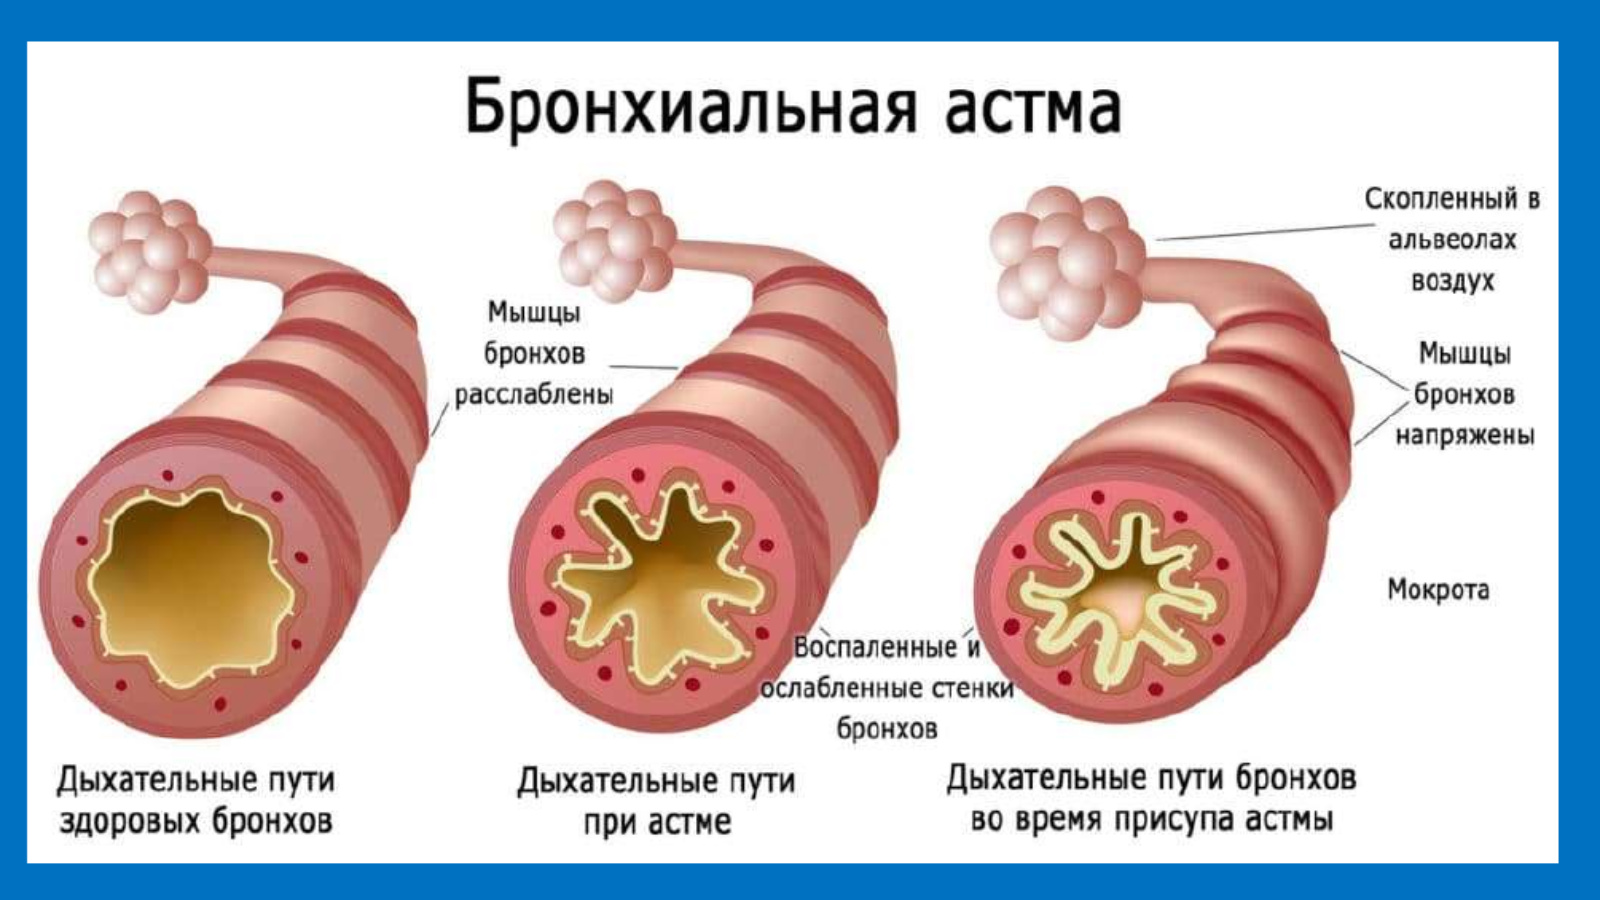

Здоровье дыхательной системы: бронхи и легкие